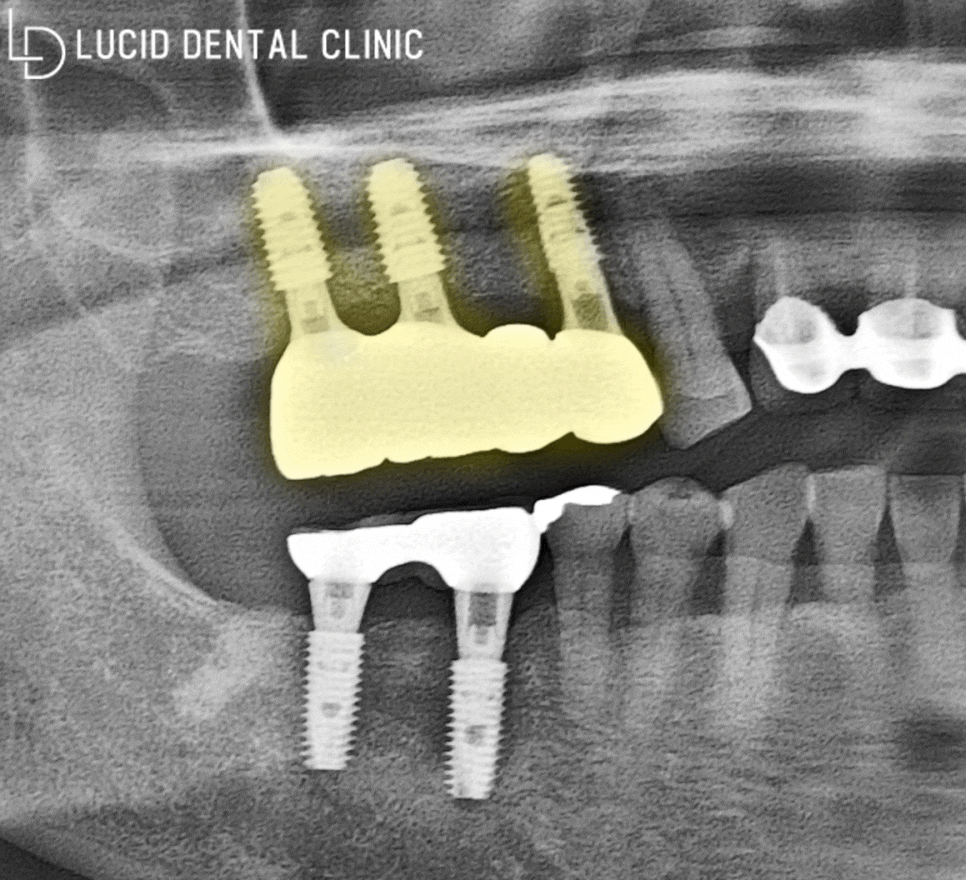

위턱 주변에 위치한 상악동을 들어올려

필요한 양만큼의 뼈 이식 재료를 채워 넣고,

임플란트 픽스처를 식립할 계획입니다 :)

- 어금니 임플란트 수술 완료

본원에선 디지털 분석

임플란트 수술을 시행하고 있으며,

오차 범위를 최소화함과 동시에

빠른 치료 기간을 기대할 수 있는데요

위와 같은 과정을 통해

임플란트 수술을 마친 뒤,

파노라마 엑스레이 사진을 통해

환자의 구강 환경을 살펴봤습니다.